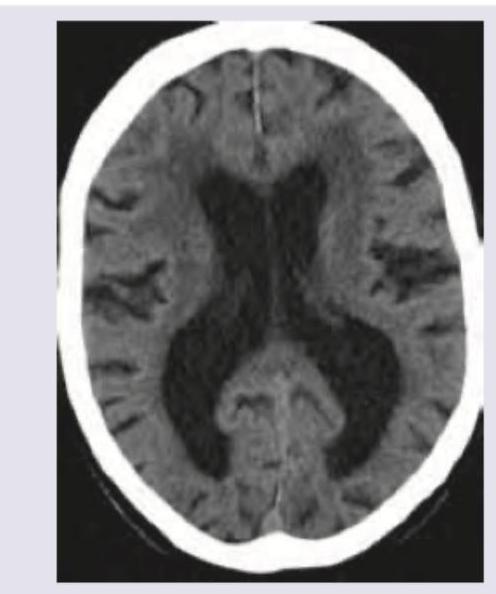

A 65-year-old man with dementia and poor hygiene due to urinary incontinence was evaluated. On examination: Deep tendon reflexes are brisk and gait apraxia with start hesitation is noted. CT scan was performed. What is the diagnosis?

Explanation: ***Normal pressure hydrocephalus*** - The classic triad of **dementia**, **gait apraxia**, and **urinary incontinence** strongly points to normal pressure hydrocephalus (NPH). The CT scan shows **ventriculomegaly out of proportion to sulcal atrophy**, a key finding in NPH. - The symptoms are often reversible with **ventriculoperitoneal shunting**, making early diagnosis crucial. *Alzheimer's disease* - While it causes **dementia**, it does not typically present with gait apraxia or urinary incontinence as prominent initial features. - CT scans in Alzheimer's usually show **diffuse cerebral atrophy**, not significant ventriculomegaly disproportionate to sulcal changes. *Multi-infarct dementia* - Characterized by a **stepwise decline** in cognitive function and focal neurological deficits related to cerebrovascular events. - CT scans would typically show evidence of **multiple infarcts** or vascular lesions, which are not explicitly described as the primary finding. *Frontal lobe tumor* - Could cause dementia and gait issues, but it would typically present with other focal neurological signs depending on the tumor's location and size, as well as **mass effect or edema** on neuroimaging. - The presented symptoms align more specifically with NPH than a generalized tumor effect without additional details.